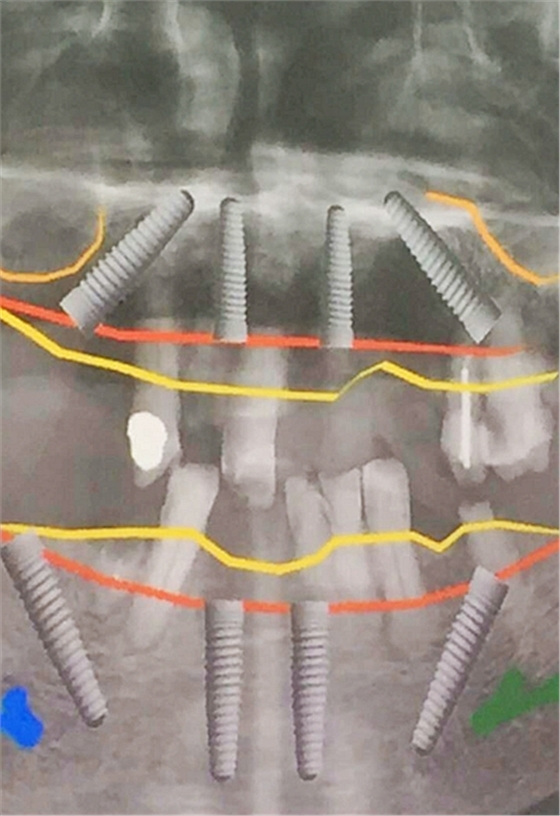

毛國(guó)斌種植病例——群討論分享

Screenshot_2017-04-25-09-45-02.pngScreenshot_2017-04-25-09-46-19.pngScreenshot_2017-04-25-09-51-57.pngScreenshot_2017-04-25-09-52-41.pngScreenshot_2017-04-25-10-06-38.pngScreenshot_2017-04-25-10-09-20.png

Screenshot_2017-04-25-10-12-47.pngScreenshot_2017-04-25-10-16-29.pngScreenshot_2017-04-25-10-19-08.pngScreenshot_2017-04-25-10-22-02.pngScreenshot_2017-04-25-10-26-11.pngScreenshot_2017-04-25-10-26-35.png

Screenshot_2017-04-25-10-34-15.pngScreenshot_2017-04-25-10-37-02.pngScreenshot_2017-04-25-10-38-17.pngScreenshot_2017-04-25-10-43-56.pngScreenshot_2017-04-25-10-45-02.png

mmexport1493090938783.jpgmmexport1493090943165.jpg

mmexport1493090947523.jpgmmexport1493090952079.jpg

mmexport1493090960504.jpgmmexport1493090963186.jpg

mmexport1493090967371.jpgmmexport1493090969886.jpg

mmexport1493090972304.jpgmmexport1493090974802.jpg

mmexport1493090981101.jpg

mmexport1493090983321.jpgmmexport1493090991830.jpg

mmexport1493090994026.jpgmmexport1493090985721.jpg

mmexport1493091008273.jpgmmexport1493091010574.jpg

江思玉整理群種植病例